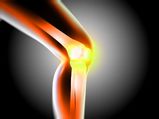

Natural Remedies For Knee Pain

Natural Remedies For Knee Pain -

Is Threadmill Harmful For The Knees?

Is Threadmill Harmful For The Knees? -

10 Best Ways To Take Care Of Your Joints

10 Best Ways To Take Care Of Your Joints -